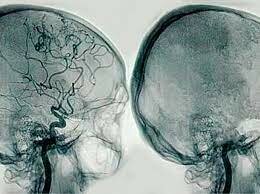

fue creada en 1927 por el neurólogo Egas Moniz para diagnosticar trastornos cerebrales desde tumores hasta malformaciones vasculares, se obtuvo el éxito con un paciente de 20 años donde inyectaron el medio de contraste y obtuvieron una imagen lateral que evidencio la desviación de la arteria cerebral media.

Angiografía cerebral

En 1934 se reportó el trabajo de la angiografía cerebral donde se describieron las fases arterial, capilar y el primer o segundo campo venoso.